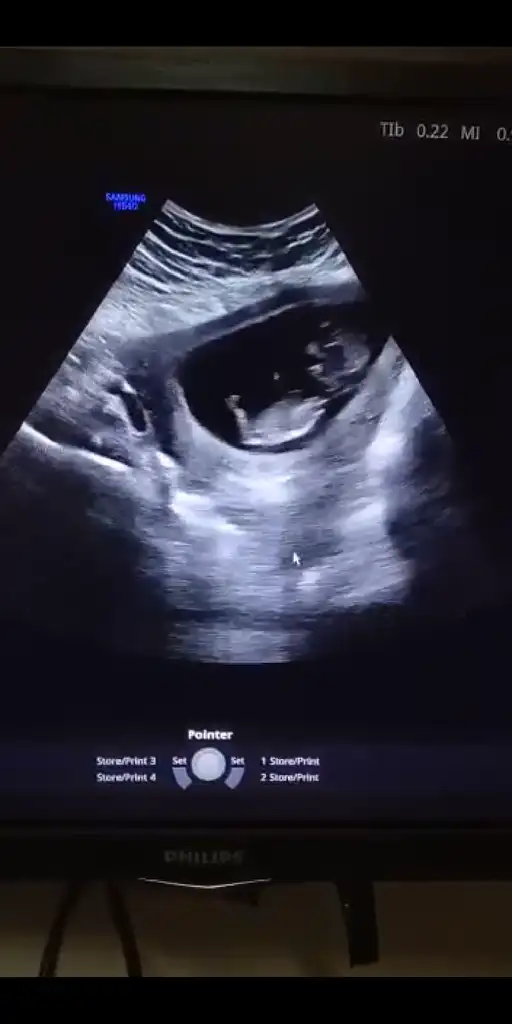

Nub yöntemine göre cinsiyet tahmini

Gittim canim dr kiz gibi dedi ama kesin soyleyebilmem icin 16.haftayi bekleyecegiz dedi ama nubu bana gore karsiya bakiyor onda da kesin konusmadi erkek olsa yanilma olmaz bu haftalarda ama bazen kizda yanilma olabilir bekleyelim dedi

Canım bencede kız.diğer nub teorisinde de belliydi.hatta sana kesin kız demiştim.nubu bariz paraleldi.ben öyle gördüm yani.şimdi bi kızın olduğu için eşinde sende erkek bebek istiyorsunuz tabi,insan olmayanı istiyor her zaman.ama bana göre cok şanslısın.kız cocuğu rahmettir,berekettir.benimde bi kızım var.keza senin de öyle.ne denli tatlılar biliyoruz.şükürler olsun yaradana.

Kesin kız canım o bebiş, doktorda söylerken emin bi şekilde söylemiş.anneolmakmucızenin en son ki mesajında öyle yazıyor. Nub bariz paralel. 😁😁 olabilir arada yanılabiliriz sıkıntı yok🤗